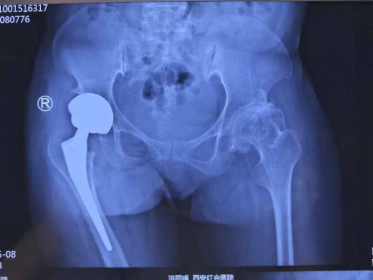

该患者其有明确家族史,结合患者病史、查体、影像学检查及基因检测结果确诊MED。该患者髋、膝、踝关节均存在明显畸形,前期在当地医院已行胫骨截骨矫形手术,目前以右髋关节疼痛为主,需行全髋置换手术治疗。由于患者术前髋部病变严重且合并股骨近端畸形,术中需特别注意臼杯安装角度及股骨柄植入方向,虽然DAA全髋置换手术难度大,但是能更少的损伤髋部软组织,术后体位无限制,患者早期康复锻炼效果更好。患者右侧肢体短缩,术中尽量延长患肢以改善下肢不平衡,使其能更快地回归正常生活、工作,充分体现了医疗团队的技术和对患者全面关怀的人文理念。

李辉主任医师介绍,MED的髋关节置换绝非标准手术的简单复制,需个体化应对三大核心:假体选择、生物力学重建以及康复锻炼,三者缺一不可,患者才能获得更好的术后功能。

郝林杰副主任医师补充,MED并非“不治之症”,早期通过影像学动态监测(如X线等)和基因检测可明确诊断,早期治疗可显著延缓病情进展,对于中晚期患者,个性化手术联合康复治疗能有效改善关节功能,本例手术需兼顾骨骼形态矫正与关节功能重建,技术难度极高,手术的成功得益于团队精湛的手术技术和充分的术前准备,我们将不断提高手术技术,结合科技的发展为患者提供更优解决病痛的治疗方案。